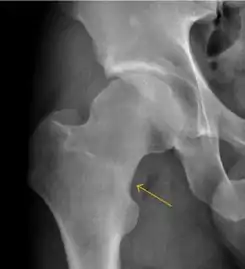

- Slipped capital femoral epiphyses (SCFE)

Slipped capital femoral epiphyses (SCFE) usually affect 11- to 14-year-old adolescents (Figure 4). Radiographs may show widening and irregularity of the physis and posterior inferior displacement of the capital femoral epiphysis. On the AP view Klein’s line, tangent to the lateral aspect of the femoral neck, does not intersect the femoral head indicating that it is displaced. SCFE may compromise the blood supply to the femoral head and cause avascular necrosis, mainly when there is instability between the fragments.[1]

Figure 4: (a) X-ray of a 10-year-old child with left hip pain. It was considered normal at emergency despite the widening of the left physis (arrow). Two weeks later epiphysiolysis was evident (b). Despite appropriate surgical reduction (c) osteonecrosis developed and femoral head collapsed 1 month later (d).[1]